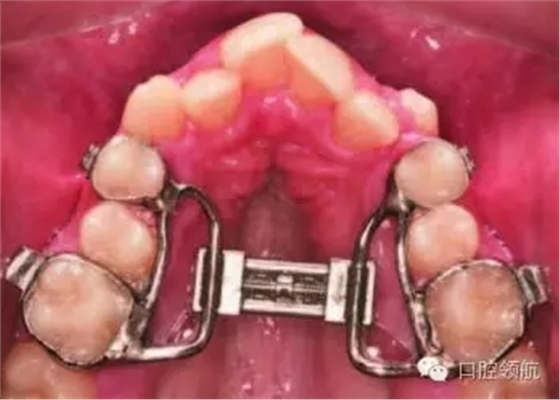

● 上頜快速擴(kuò)弓(圖3.14)。

快速上頜擴(kuò)弓器(Rapid Maxillary expansion,RME)是一種在生長發(fā)育期使用的牙弓擴(kuò)大裝置。其功能的發(fā)揮依賴于腭中縫這一結(jié)構(gòu),而后者經(jīng)解剖學(xué)研究證實(shí)在15歲之前一直明顯存在。該矯治器通常由第一前磨牙和第一磨牙上的帶環(huán)固定,也可粘結(jié)在牙齒上。快速上頜擴(kuò)弓器擴(kuò)大腭中縫的效率為每天0.5~1mm,而使用活動矯治器的慢速上頜擴(kuò)弓器則為每周0.25~0.5mm。適當(dāng)?shù)倪^矯治對抵抗牙弓狹窄的復(fù)發(fā)是有利的。為保持?jǐn)U弓療效,矯治裝置應(yīng)在主動擴(kuò)弓治療結(jié)束3個月后拆除。還可使用橫腭桿防止牙弓狹窄復(fù)發(fā),但其效果并不確切。

擴(kuò)弓作用通過牙齒的整體和傾斜移動實(shí)現(xiàn)。牙齒的傾斜移動并不穩(wěn)定,并有可能造成支持尖下垂使覆牙合變淺??焖贁U(kuò)弓中,牙齒傾斜移動與整體移動的比例可達(dá)1∶1,但在使用活動矯治器和擴(kuò)弓螺旋的慢速擴(kuò)弓治療中,牙齒傾斜移動所占比例遠(yuǎn)大于整體移動(Frank and Engel, 1982)??焖贁U(kuò)弓裝置較為常用的固位方法是帶環(huán)固定法;但研究顯示粘結(jié)固位能夠通過覆蓋后牙的面來減少打開咬合的副作用。

○ 通過帶環(huán)固位或粘結(jié)固位的RME。

● 患者需要超過4mm的擴(kuò)弓量。

● 患者年齡適合快速擴(kuò)弓,并且腭中縫較為明顯。

● RME能提供較多的牙齒整體移動,以減輕對咬合打開的副作用,這對維持該患者原本較淺的覆牙合有利。